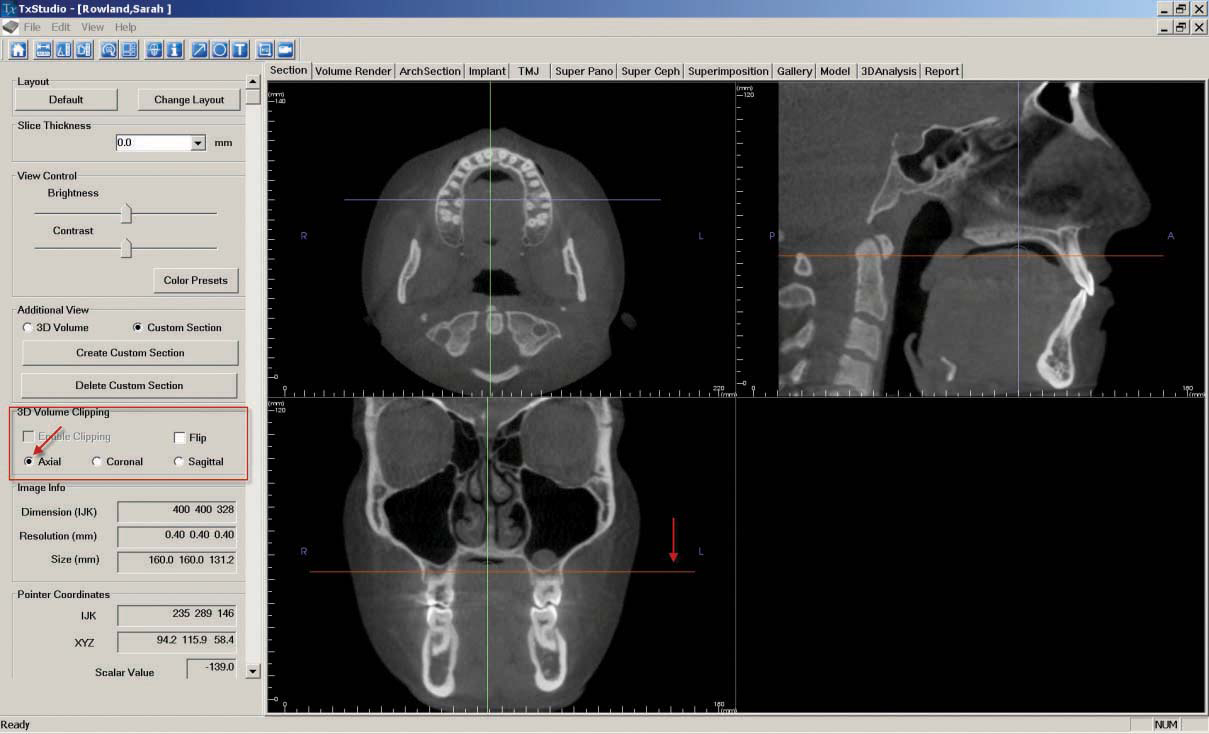

c. The "Coronal Slice" is created by navigating to the "Section" tab. First, ensure the patient is correctly oriented. To adjust the orientation, click the "Reorientation" icon at the top of the screen.

Once the orientation is correct, adjust the orange line in the bottom left image until the top left image shows a clear view of the lower arch. Next adjust the purple line in the upper left image while looking at the image below until there is a clear coronal slice of the first molars.

In the "3D Volume Clipping" section on the left-hand side of the screen, select "Coronal."

If desired, click the "Toggle Cursor Visibility" icon to remove reference lines. As described in step 7, "Capture to Gallery" and select "Coronal" in the "Select Image to Capture" pop-up window. Click "OK," then name the image "Coronal Slice."

d. To create the "Axial Slice," stay in the "Section" tab and adjust the orange line in the lower left image until the upper left image shows a clear view of the mandibular bone. In the "3D Volume Clipping" section on the left-hand side of the screen, select "Axial."

e. If desired, click the "Toggle Cursor Visibility" icon to remove reference lines. As described in step 7, "Capture to Gallery" and select "Axial" in the "Select Image to Capture" pop-up window. Click "OK," then name the image "Axial Slice."

f. The "Sagittal Slice" is also created in the "Section" tab. Adjust the green line in the center of the bottom left image until the upper right image shows a clear view of the right centrals. In the "3D Volume Clipping" section on the left-hand side of the screen, select "Sagittal."

If desired, click the "Toggle Cursor Visibility" icon to remove reference lines. As described in step 7, "Capture to Gallery" and select "Sagittal" in the "Select Image to Capture" pop-up window. Click "OK," then name the image "Sagittal Slice."